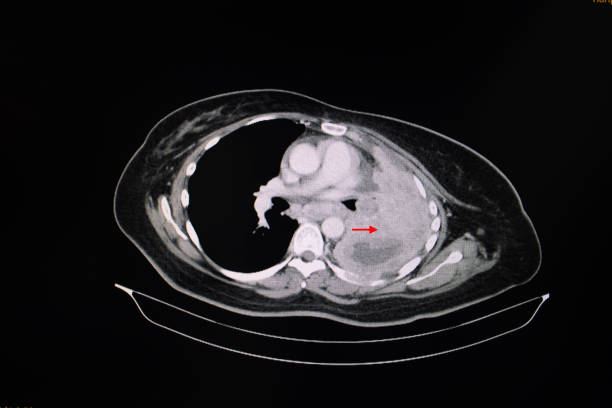

뇌경색은 뇌의 혈관이 막혀 뇌조직에 산소와 영양분이 제대로 공급되지 않아 발생하는 심각한 질환입니다. 특히 한국에서는 고령화와 함께 고혈압, 당뇨병 등 만성질환의 증가로 인해 뇌경색 환자의 수가 급격히 늘어나고 있습니다. 이는 일상생활에 큰 영향을 미치고, 적절한 초기 대응과 치료가 이루어지지 않으면 치명적인 후유증을 남길 수 있습니다. 따라서 뇌경색의 초기 증상을 정확히 파악하고, 적절한 치료 방법을 이해하며, 후유증을 최소화하기 위한 방법을 아는 것이 매우 중요합니다.

▌ 뇌경색의 치료 방법

뇌경색의 치료는 발생 원인과 환자의 상태에 따라 달라질 수 있으며, 크게 약물 치료와 수술적 치료로 나뉩니다.